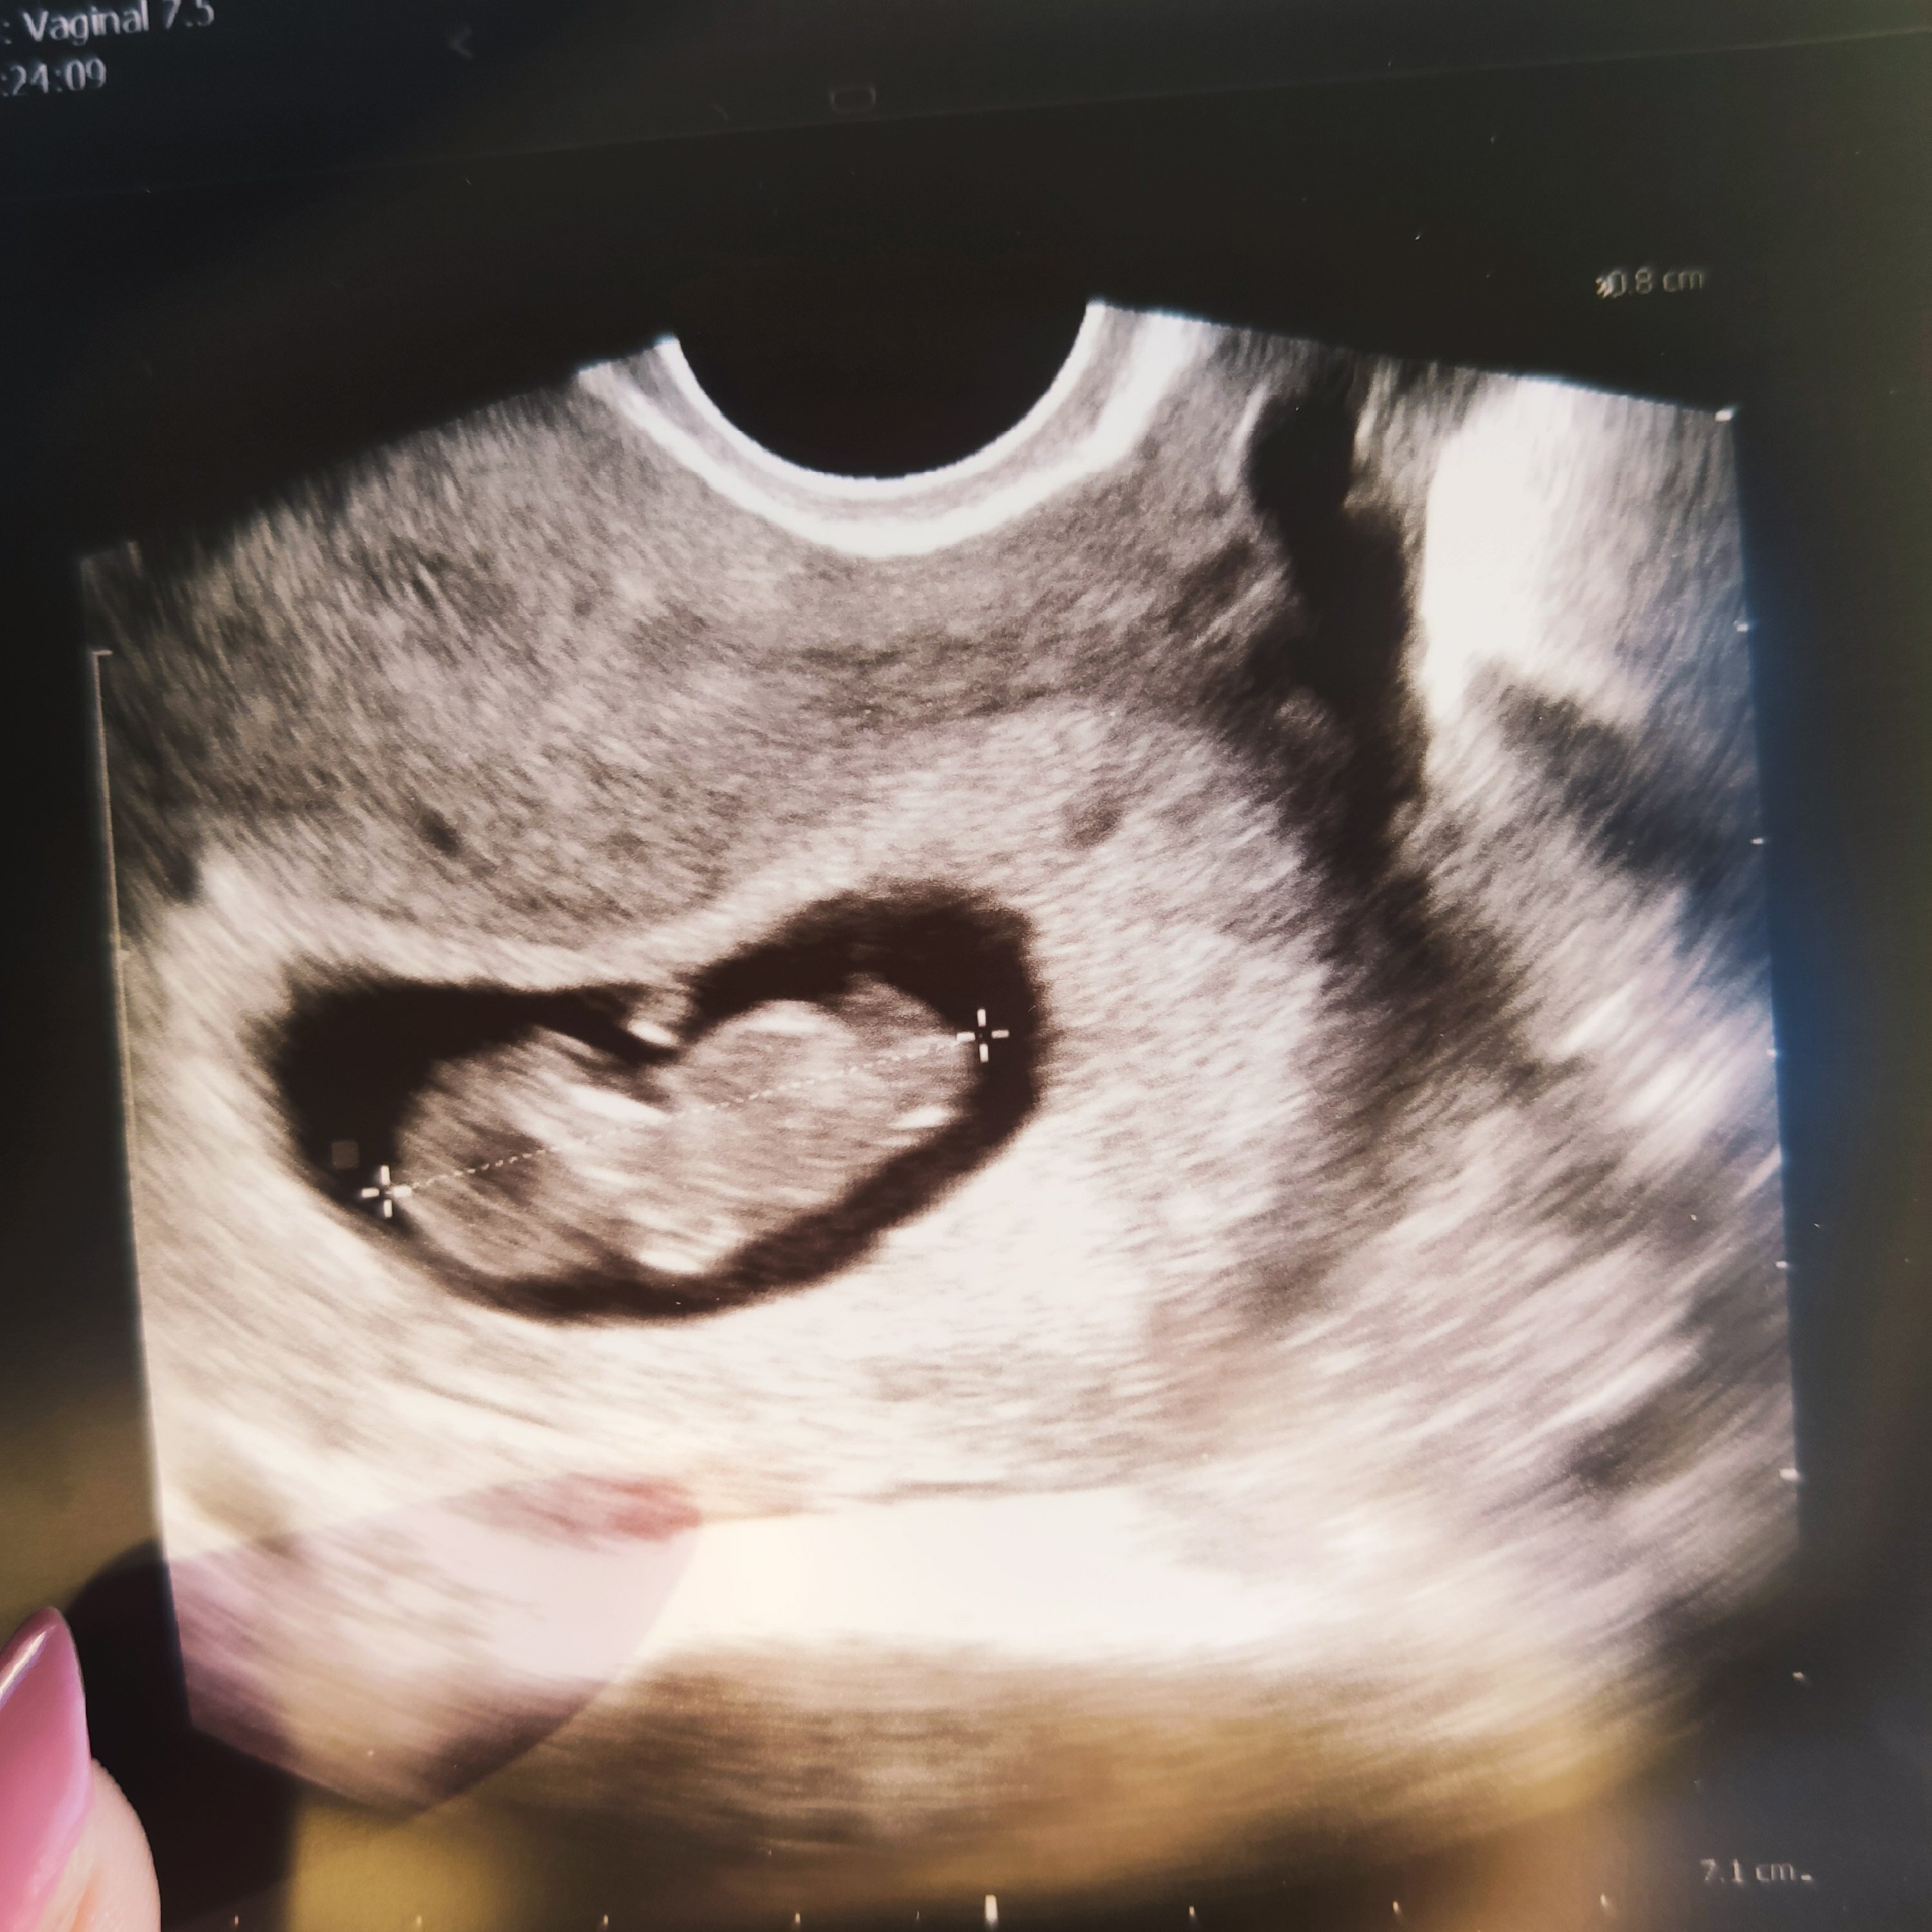

Dziewczyny walczcie!! Nie poddawajcie się!! Ja miałam wiele razy chwilę słabości.. płacz, rozpacz, obwinianie się.. powiedziałam sobie że jeśli nie spróbuję wszystkiego to będę sobie pluła w brodę.. po tylu niepowodzeniach, poronieniu ciężko jest myśleć pozytywnie.. ale udało się! Boje się z wizyty na wizytę, czasami wyje dzień wcześniej sama nie wiem dlaczego, boje się że coś się stanie i skoro tyle złego to czemu teraz ma być dobrze.. a póki co jest, moje maleństwo ma dzisiaj 3cm, serce bije jak dzwon :) oboje z mężem jesteśmy przestraszeni a zarazem przeszczęśliwi i oby tak zostało🙏❤️ Tego też Wam życzę, zobaczycie że po tym całym maratonie czeka podium ✊✊